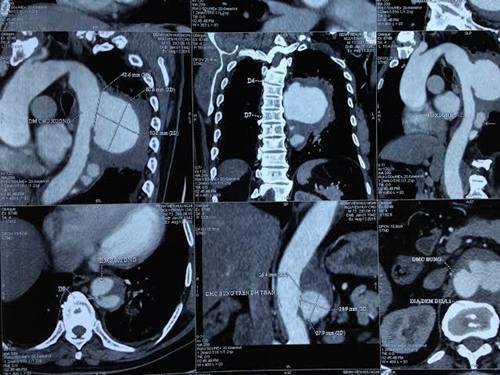

Hình ảnh trước can thiệp đặt stent graft của bệnh nhân Nguyễn Huy Ch. |

Theo một bác sĩ BV Hữu Nghị chia sẻ, ngày 13/8, bệnh nhân có tên Nguyễn Huy Ch., 73 tuổi, được chuyển từ Sơn La đến Bệnh viện Hữu Nghị vì bệnh lý đường hô hấp trong tình trạng rất nguy kịch, kết quả chụp XQ tim phổi cho thấy có đám mờ lớn bên phổi trái, nghĩ nhiều đến u phổi hoặc viêm phổi. Kết quả chụp MSCT 64 slide/s ngực - bụng cho thấy, bệnh nhân có 3 ổ giả phình ở động mạch chủ ngực, 1 ổ giả phình động mạch chủ bụng. Ổ giả phình lớn nhất có vị trí trong lồng ngực bệnh nhân kích thước 74x60mm, chèn ép gây xẹp phổi trái, rỉ máu từ ổ phình gây tràn máu màng phổi trái, có dấu hiệu dọa vỡ túi phình.